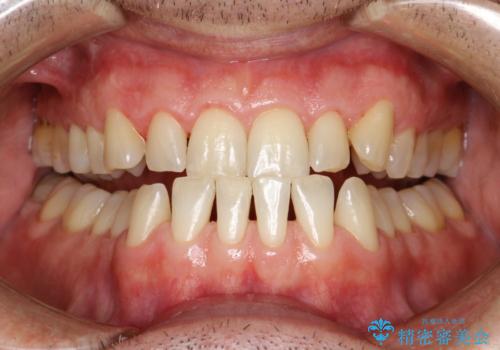

歯磨き中に血が出る PMTCで歯石除去

- 毎日の歯磨きの際に出血する。歯科でにクリーニンングをしばらくしていないとのことでした。PMTC60分コースを行いました。

そのため重要なのが、毎日の歯磨きで可能な限り汚れを取り除くこと・定期的に歯科医院で歯周病の検査をしたり、歯石除去や歯茎の炎症を取り除くことです。